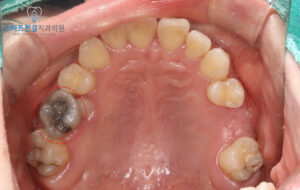

확인해 보니 큰 어금니에는

오래전에 치료했던 광범위한

아말감이 남아 있는 상태였어요.

아말감은 과거에

많이 사용되던 재료이지만,

시간이 오래 지나면 치아와

재료 사이에 미세한 틈이

생길 수 있어요.

인접한 작은 어금니가

잇몸 속에 묻혀 있는

미맹출 상태였기 때문이에요.